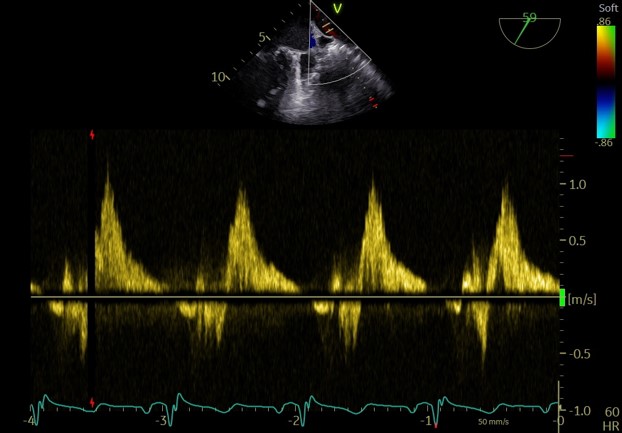

术前肺静脉频谱

术后肺静脉频谱